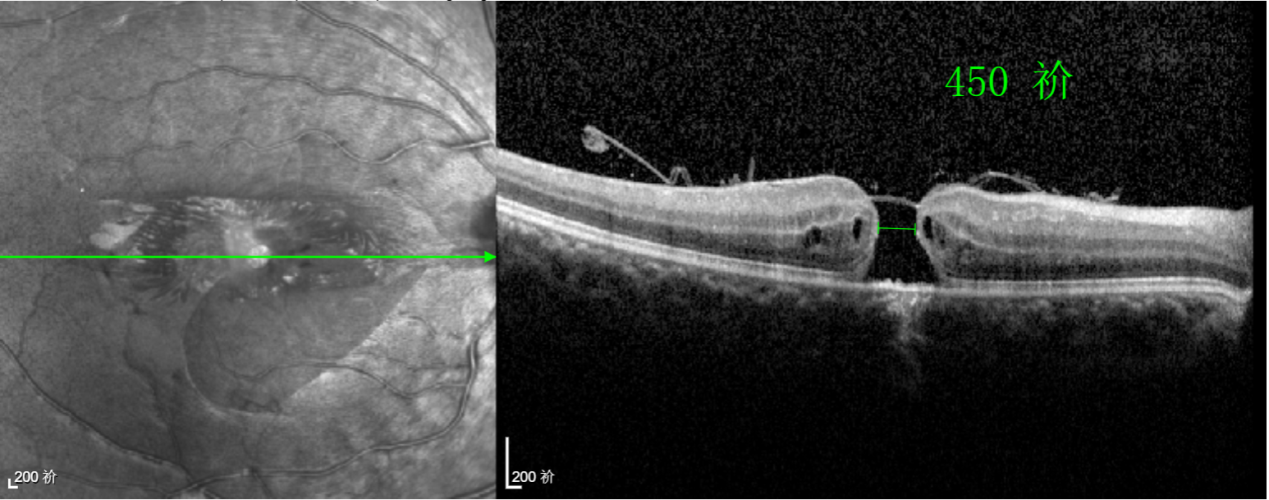

經(jīng)過詳細的檢查和評估,王曉波主任決定采用“內(nèi)界膜翻轉(zhuǎn)覆蓋聯(lián)合粘彈劑固定術(shù)”為誠誠進行治療。

術(shù)中,醫(yī)生精細剝離黃斑區(qū)的內(nèi)界膜后,并非直接丟棄,而是巧妙地給它翻個面,讓它變成一塊天然“創(chuàng)可貼”,嚴密覆蓋在黃斑裂孔的表面。覆蓋的內(nèi)界膜像微型支架一樣撐住裂孔邊緣,防止它擴大;同時,這層膜本身含有能促進生長的“養(yǎng)分”,能顯著刺激裂孔周圍的視網(wǎng)膜組織像爬山虎一樣快速生長、蔓延過來,最終把裂孔“補”好。

除此之外,利用自體組織覆蓋為黃斑裂孔提供了理想的愈合環(huán)境,裂孔閉合速度顯著快于傳統(tǒng)方法。誠誠接受手術(shù)24小時后,檢查可見內(nèi)界膜瓣位置良好;術(shù)后1個月,黃斑裂孔已經(jīng)閉合,視力恢復(fù)到0.5;術(shù)后兩個月,視力進一步提升到0.7。